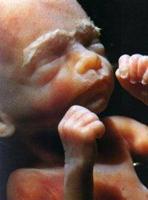

Eight-week pre-born

baby

At eight to nine weeks the eyelids have

begun forming and hair appears. By the ninth and tenth weeks the

preborn child sucks her thumb, turns somersaults, jumps, can squint

to close out light, frown, swallow, and move her tongue.